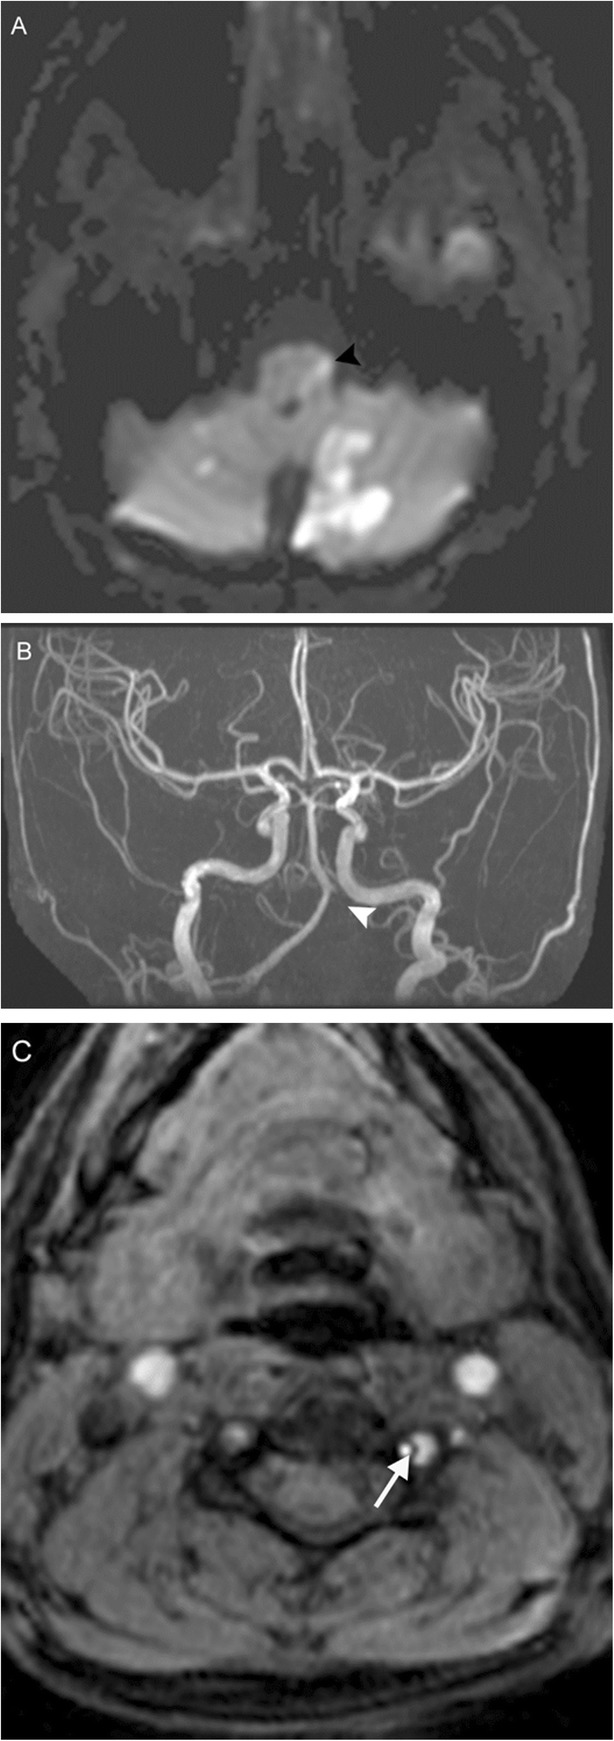

The posterior inferior cerebellar artery (PICA) territory includes the inferior occipital surface of the cerebellar hemisphere and inferior vermis, while perforators off the intracranial vertebral (V4 segment) and basilar arteries supply the brainstem. Occlusion of the distal V4 segment or PICA can result in infarction of the lateral medulla (Fig. 11); this is characterized by a constellation of symptoms known as lateral medullary or Wallenberg syndrome [17]. Due to involvement of the nucleus ambiguus, patients will have ipsilateral bulbar weakness affecting the muscles of the soft palate and pharynx, resulting in dysphonia, dysphagia, and dysarthria. Other symptoms include autonomic dysfunction, ipsilateral Horner’s sign (meiosis, ptosis, enophthalmos, anhydrosis), ipsilateral facial and contralateral truncal/appendicular sensory disturbance, and vestibulocerebellar symptoms such as ataxia and vertigo (patients will “fall toward the lesion”).

Fig. 11.

Lateral medullary infarction. A 33-year-old woman with history of migraines presenting with acute onset vertigo, nausea, weak voice/swallow, and left extremity sensorimotor deficits after chiropractic manipulation. Diffusion-weighted MRI (a) reveals numerous acute embolic infarctions involving the bilateral cerebellar hemispheres and bilateral thalami, with notable involvement of the left PICA territory including the left lateral medulla (black arrowhead). TOF MRA MIP image (b) reveals absence of flow related enhancement within the left V4 segment and PICA (white arrowhead). Axial TOF image (c) reveals small caliber flow within the residual true lumen (white arrow), with surrounding crescentic lower signal in the false lumen. This constellation of findings is consistent with left vertebral artery dissection with showering of emboli resulting in infarction